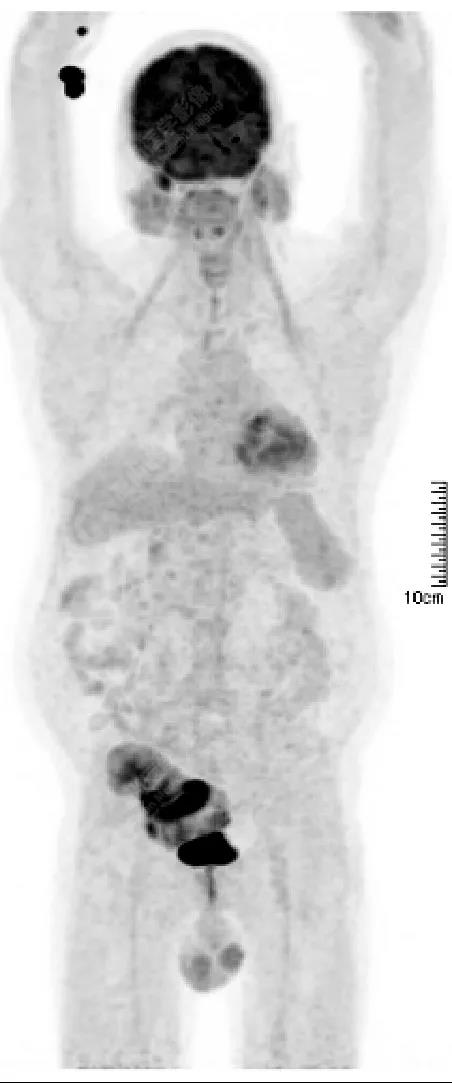

PET/CT檢查

↑移植腎下部等密度腫塊,代謝環(huán)狀增高,SUVmax13.4,中心代謝缺損

PET/CT檢查意義

發(fā)現(xiàn)全身其它部位有無結(jié)內(nèi)或結(jié)外淋巴瘤病灶。由于淋巴瘤組織多具備高代謝、大范圍無氧酵解的特性,葡萄糖需求量為正常組織細(xì)胞的20~30倍,正電子湮滅產(chǎn)生的光子信號聚集于灶區(qū),PET捕獲后可半定量分析其分布特征【4】。